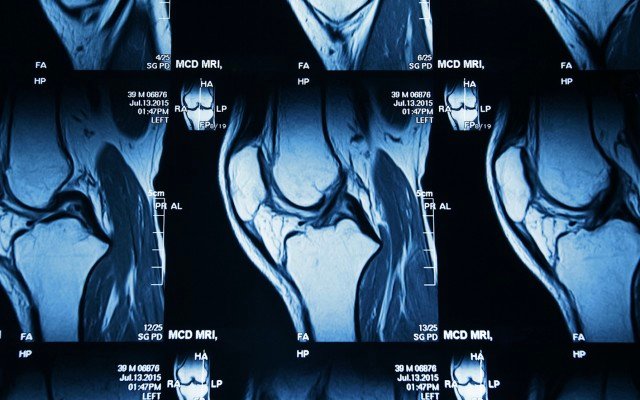

Paradigm Biopharmaceuticals’ iPPS drug reduces bone marrow lesions in hip, knee caps and ankles

Paradigm Biopharmaceuticals’ iPPS drug has resulted in a material reduction in bone marrow lesions within the knee, hip and ankle.

As it advances its injectable Pentosan Polysulfate (iPPS) drug towards commercialisation, Paradigm Biopharmaceuticals (ASX: PAR) has noted a clinically meaningful decrease in bone marrow lesions in hip, knee caps and ankles for patients enrolled in the company’s phase 2b clinical trial.

Under the Therapeutic Goods Administration’s special access scheme, patients who have received iPPS injections have reported reduced bone marrow lesions in other sites of the body other than the knee, which has been the primary focus of clinical trials.